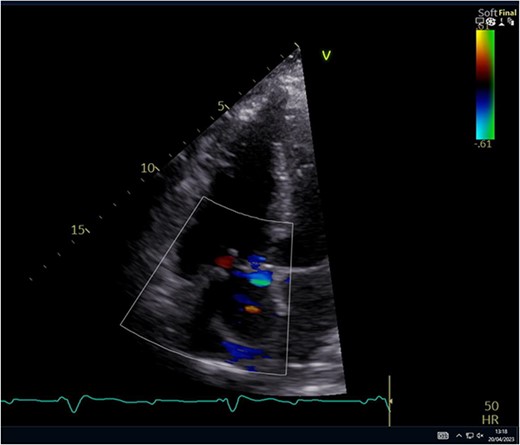

He had a redo-median sternotomy. Cardiopulmonary bypass was instituted through aortic cannulation connected to the bypass machine via a bifurcated arterial line along with the femoral ECMO cannula. The SVC and IVC were cannulated before opening the right atrium. The TV was inspected which revealed a flail anterior leaflet, attached to the ruptured head of the papillary muscle (Fig. 3).

Intraoperative pictures demonstrating a flail anterior leaflet attached to the ruptured head of the papillary muscle.